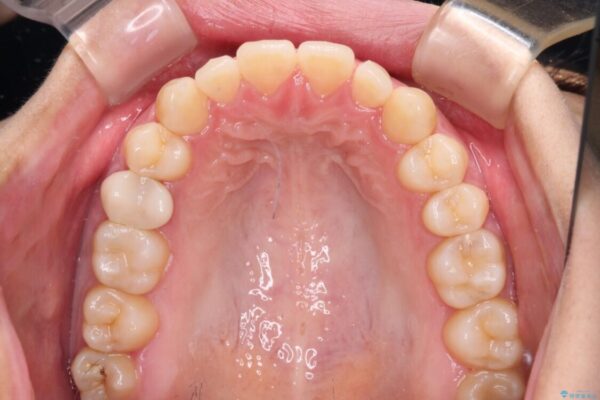

治療後

• 隙間だらけの歯列 インビザラインで改善 治療後画像